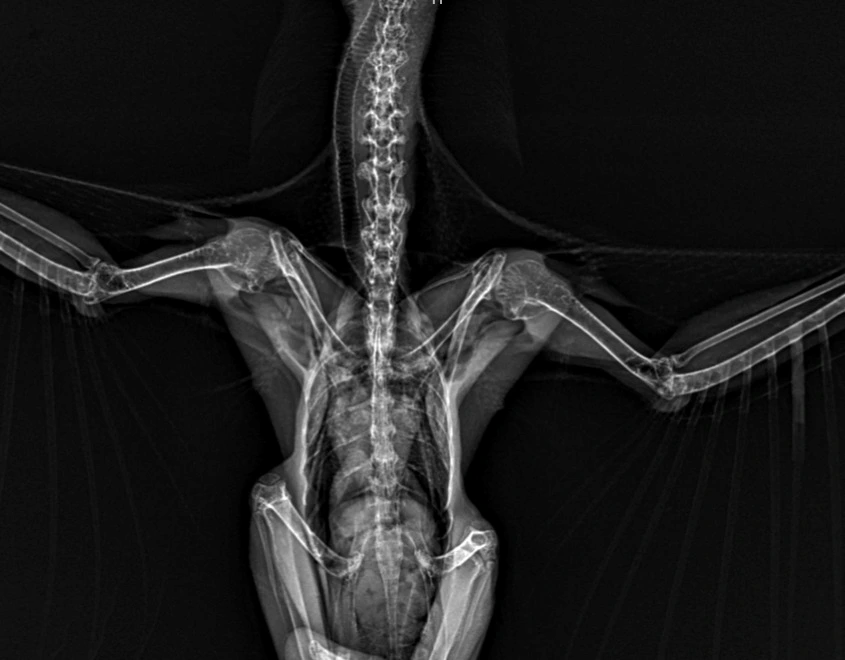

Entre os exames disponíveis estão, hemograma, radiologia, ultrassonografia, histopatologia, citopatologia, imunologia, microbiologia e PCR.